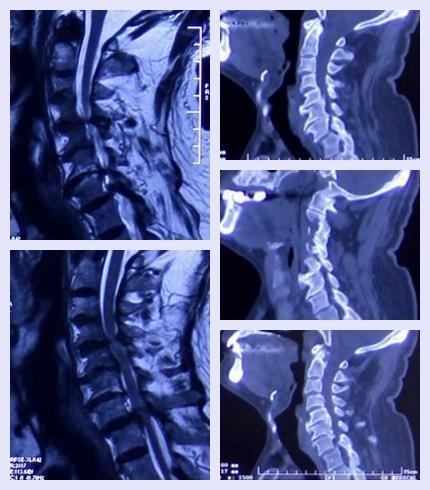

疾病介绍:颈椎管狭窄

近日,接诊一例主诉为“左上肢麻木+右下肢无力”的患者,经诊断患者被确诊为颈椎管狭窄且以造成神经根明显受压,建议手术治疗。术后患者症状缓解明显,无不适。

患者陕西临潼人,老年男性,70岁。1年前出现左上肢麻木及右下肢无力症状,就诊于当地某医院被诊断为“颈椎病”并做颈椎病对症治疗。1年来,治疗未见明显效果,患者病情呈现进行性加重。患者为进一步诊断、治疗前来唐都医院。

结合患者病史、体征等初步诊断为颈椎管狭窄。集合影像学检查确诊为颈椎管狭窄。

影像学